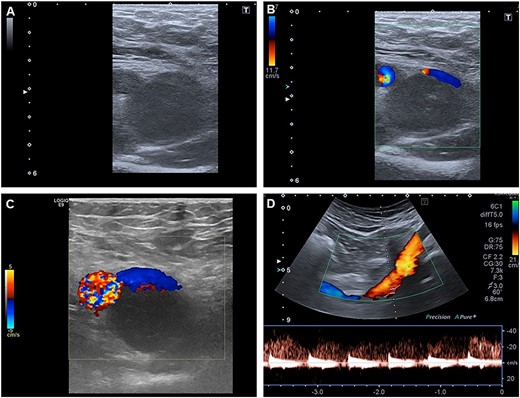

A 53-year-old, otherwise healthy patient presented with a swelling of the right foot and ankle since 4 months. The patient denied previous trauma, B-symptoms and intermittent claudication. Clinical examination showed edema of the aforementioned regions, and no signs of infection. Deep vein thrombosis was ruled out by ultrasound. X-rays and serological examinations showed no signs of arthritis. A CT-scan was performed 1 month after initial presentation due to progressive swelling of the leg and showed a change in diameter of the common femoral vein due to compression of a hyperechogenic structure in the groin. These findings were confirmed by duplex sonography, showing a structure with a diameter of 3 cm compressing the femoral vein (Fig. 1).

Duplex sonography shows a mass compressing the femoral vein from dorsally.